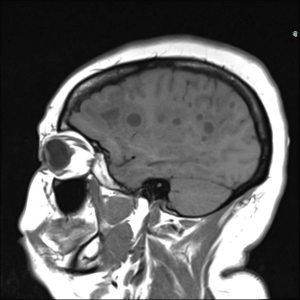

41-year-old female presents with chronic headache.